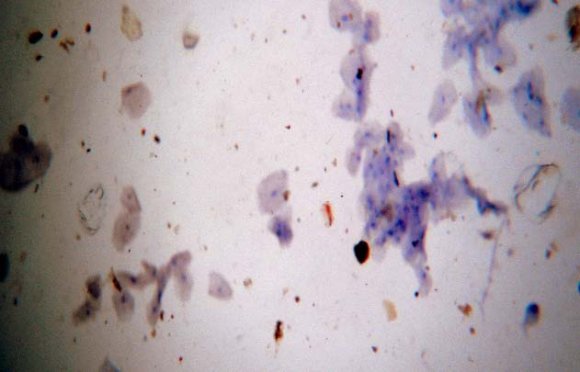

Modified Rhodamine stain is a copper specific stain and histologically demonstrates copper in the tissues. [12] Comparision of different histochemical staining methods has shown modified Rhodamine technique to be the method of choice for the detection of copper. [13] Copper appears red to orange-red stain and the nucleus was stained blue. [4] Irons RD et al have concluded that the Rhodamine method was found to produce the most reproducible results and a linear relationship between microscopical evaluation of the stain and actual tissue copper levels was observed. They considered that the Rhodamine method is applicable for the semiquantitative evaluation of tissue copper and provides a satisfactory screening method for the identification of abnormal tissue copper levels. They observed that a minimum of 60 g of copper per gram of tissue has to be present for cytochemical identification of copper using Rhodamine staining technique. [14] Copper is widely used in household plumbing materials. It is also enters the water ("leaches") through contact with the plumbing. Copper leaches into water through corrosion. Copper can leach into water primarily from pipes, but fixtures and faucets (brass), and fittings can also be a source. The amount of copper in water also depends on the types and amounts of minerals in the water, how long the water stays in the pipes, the amount of wear in the pipes, the water's acidity and its temperature. Safety of leached copper does not appear to be an issue since studies have shown that the current WHO guideline of 2 mg Cu/L is safe. [15,16] Arakeri G et al (2014) [17] conducted a study to evaluate that OSMF was significantly associated with a raised concentration of copper in drinking water. The study was carried out in a heterogeneous population in Hyderabad-Karnataka, India, a region with a high incidence of the condition. They evaluated 3 groups, each of 100 patients: those with OSMF who chewed gutkha, those who chewed gutkha but did not have OSMF, and healthy controls who did not chew gutkha. The difference between the groups in the mean concentration of copper in water measured by atomic absorption spectrometry was significant (p<0.001). There were also significant differences between the groups in mean concentrations of serum copper, salivary copper, and ceruloplasmin (p<0.001). The results confirm that copper in drinking water contributes to the pathogenesis of OSMF, but ingestion of copper is unlikely to be the sole cause.

In the present study a comparison between normal subjects, copper vessel stored water consuming and OSMF subjects showed difference in the no of squames showing positive staining. The normal subjects showed no staining (Fig1). Subjects consuming copper vessel stored water throughout the day and those consuming water stored overnight showed difference in the staining intensity (Fig 2, 3). People consuming copper vessel stored water throughout the day showed majority of squames showing dark red staining than the ones consuming water once a day(Fig4). The OSMF patients also showed positive staining but the staining was comparable with that of copper vessel subjects ( In mammals, copper can be absorbed from the stomach to the distal small intestine. A critical component of copper gastrointestinal balance involves enterohepatic circulation. At least one-half of the amount of copper reaching the small intestine reappears in the bile as strongly bound compounds, and is lost in the stool. The distribution of copper throughout the body is mediated by ceruloplasmin, albumin, and other quantitatively less important copper binders. [18] Copper added to cooked foods with high protein contents, such as chicken liver or chick peas, was more poorly absorbed by rats than copper supplied from other vegetable and animal sources. [19] A study was conducted by Janet R Hunt(2001) [20] that showed that although copper was less efficiently absorbed from a vegetarian diet than from a nonvegetarian diet, the total apparent copper absorption was greater from the vegetarian diet because of its greater copper content.